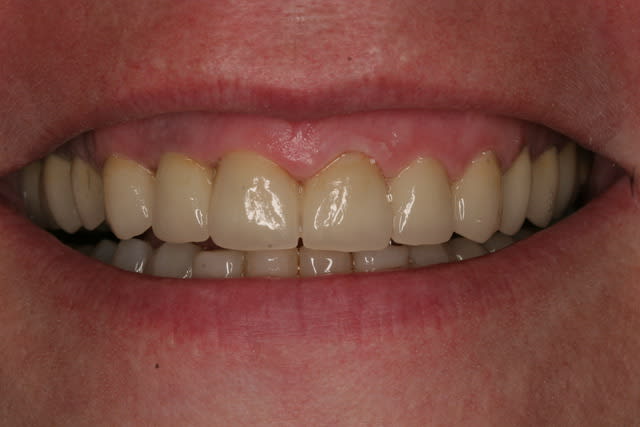

Et voila la pose , pour les habitants du nouveau monde c'est très coloré, pour les Franchouillard c'est naturel... perso je m'en fout la patiente est toute joilleuse et j'ai pas honte de moi, j'ferais encore mieux dés qu'on m'en donneras l'occasion.

Merci de m'avoir laisser finir sans me tailler un short tout de suite!